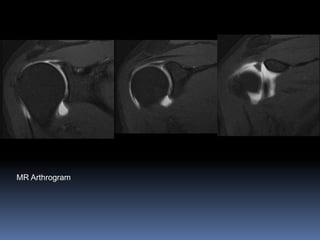

MR Arthrogram

Hyperintense signal within labrum extending

posteriorly. Indicative of SLAP lesion. (Superior Labral

anteroposterior tear)

Labrum shows several anatomical variations. Conventional MRI is not

accurate in diagnosing labral tears (40-70% sensitivity and specificity) MR

Arthrography is more accurate (90-95% sensitivity and specificity)